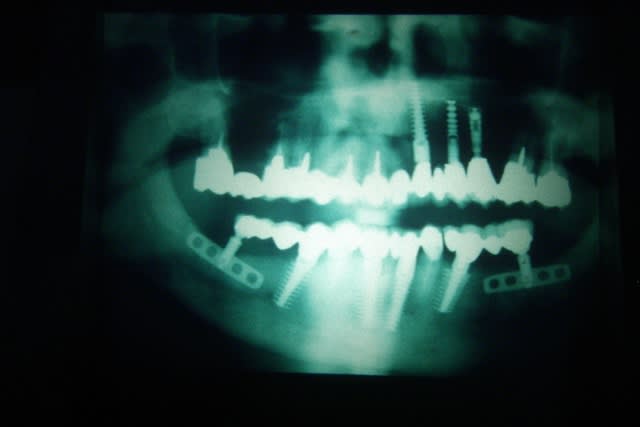

Ci joint radio de la lame. Les implants adjacants sont des implants Denar.

effectivement ça ressemble bien à du Linkow, si c'est comme pour les Tatums, pas de vis à gauche (il faut visser pour dévisser)